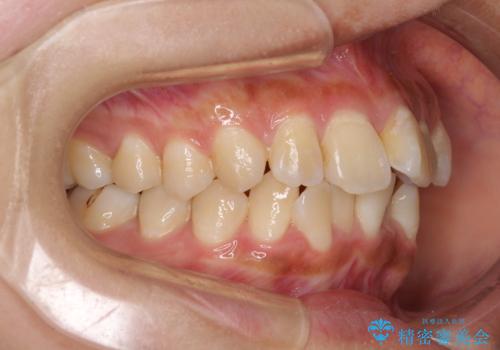

歯列は叢生が認められる程度でしたが、やや前突感があったので、少しでも口が閉じやすくなるように仕上げる方針としました。

歯磨きしやすくなるとともに、飛び出していた前歯も引っ込めて整えることができました。